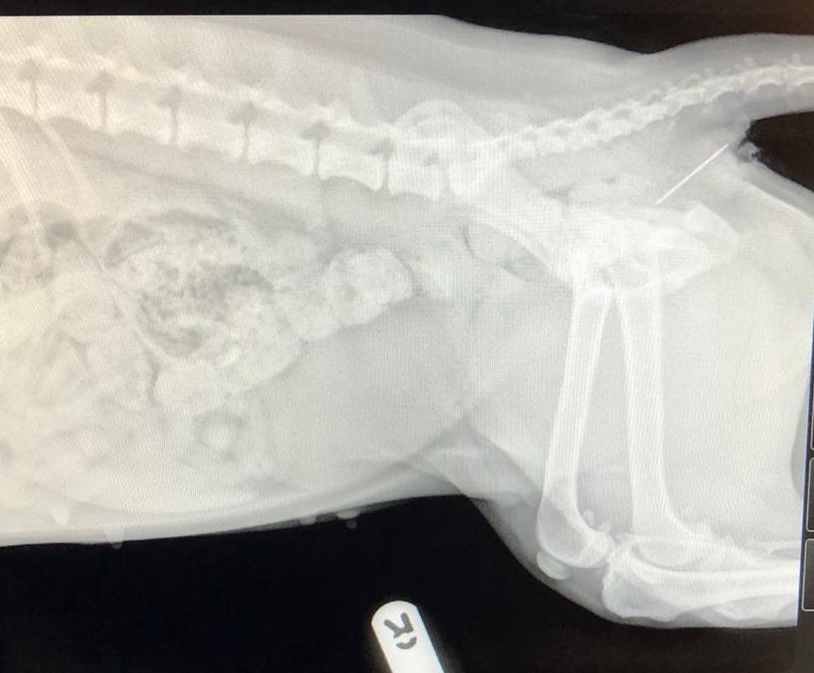

After Poppy was sedated an abdominal radiograph was performed and revealed a sewing needle was indeed attached to the end of the string! This is evident within the radiographs below. This was successfully removed and Poppy was sent home later that day with pain relief. We are pleased to report she made a full recovery.